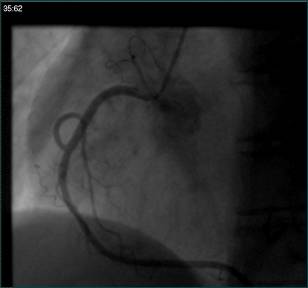

②冠脉造影:

冠脉造影未见明显异常;

⑥冠脉造影(2015.03.02)